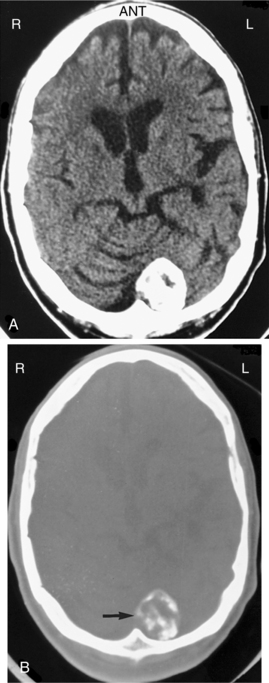

Pathogenesis.: Meningiomas originate in the arachnoid layer of the meninges and are believed to be derived from the cells and vascular elements of the meninges. Cytogenetic analysis has demonstrated multiple deletions on chromosome 22 in most people with meningioma. They are most often located between or over the cerebral hemispheres, at the skull base, or in the posterior fossa. Meningiomas are typically well-circumscribed globular masses. They may infiltrate the dura, the dural sinuses, or bone, but generally do not invade the underlying brain parenchyma. See Figs. 30-8 and 30-9 for CT scans of meningiomas. Most meningiomas grow as well-encapsulated tumors, but others develop in relatively thin sheets along the dura.

Figure 30-8 Meningioma. A, A noncontrasted computed tomographic scan shows a very dense, peripherally based lesion in the left cerebellar area. B, A bone window image obtained at the same level shows that the density is due to calcification within this lesion. (From Mettler FA Jr: Essentials of radiology, ed 2, Philadelphia, 2005, Saunders.)